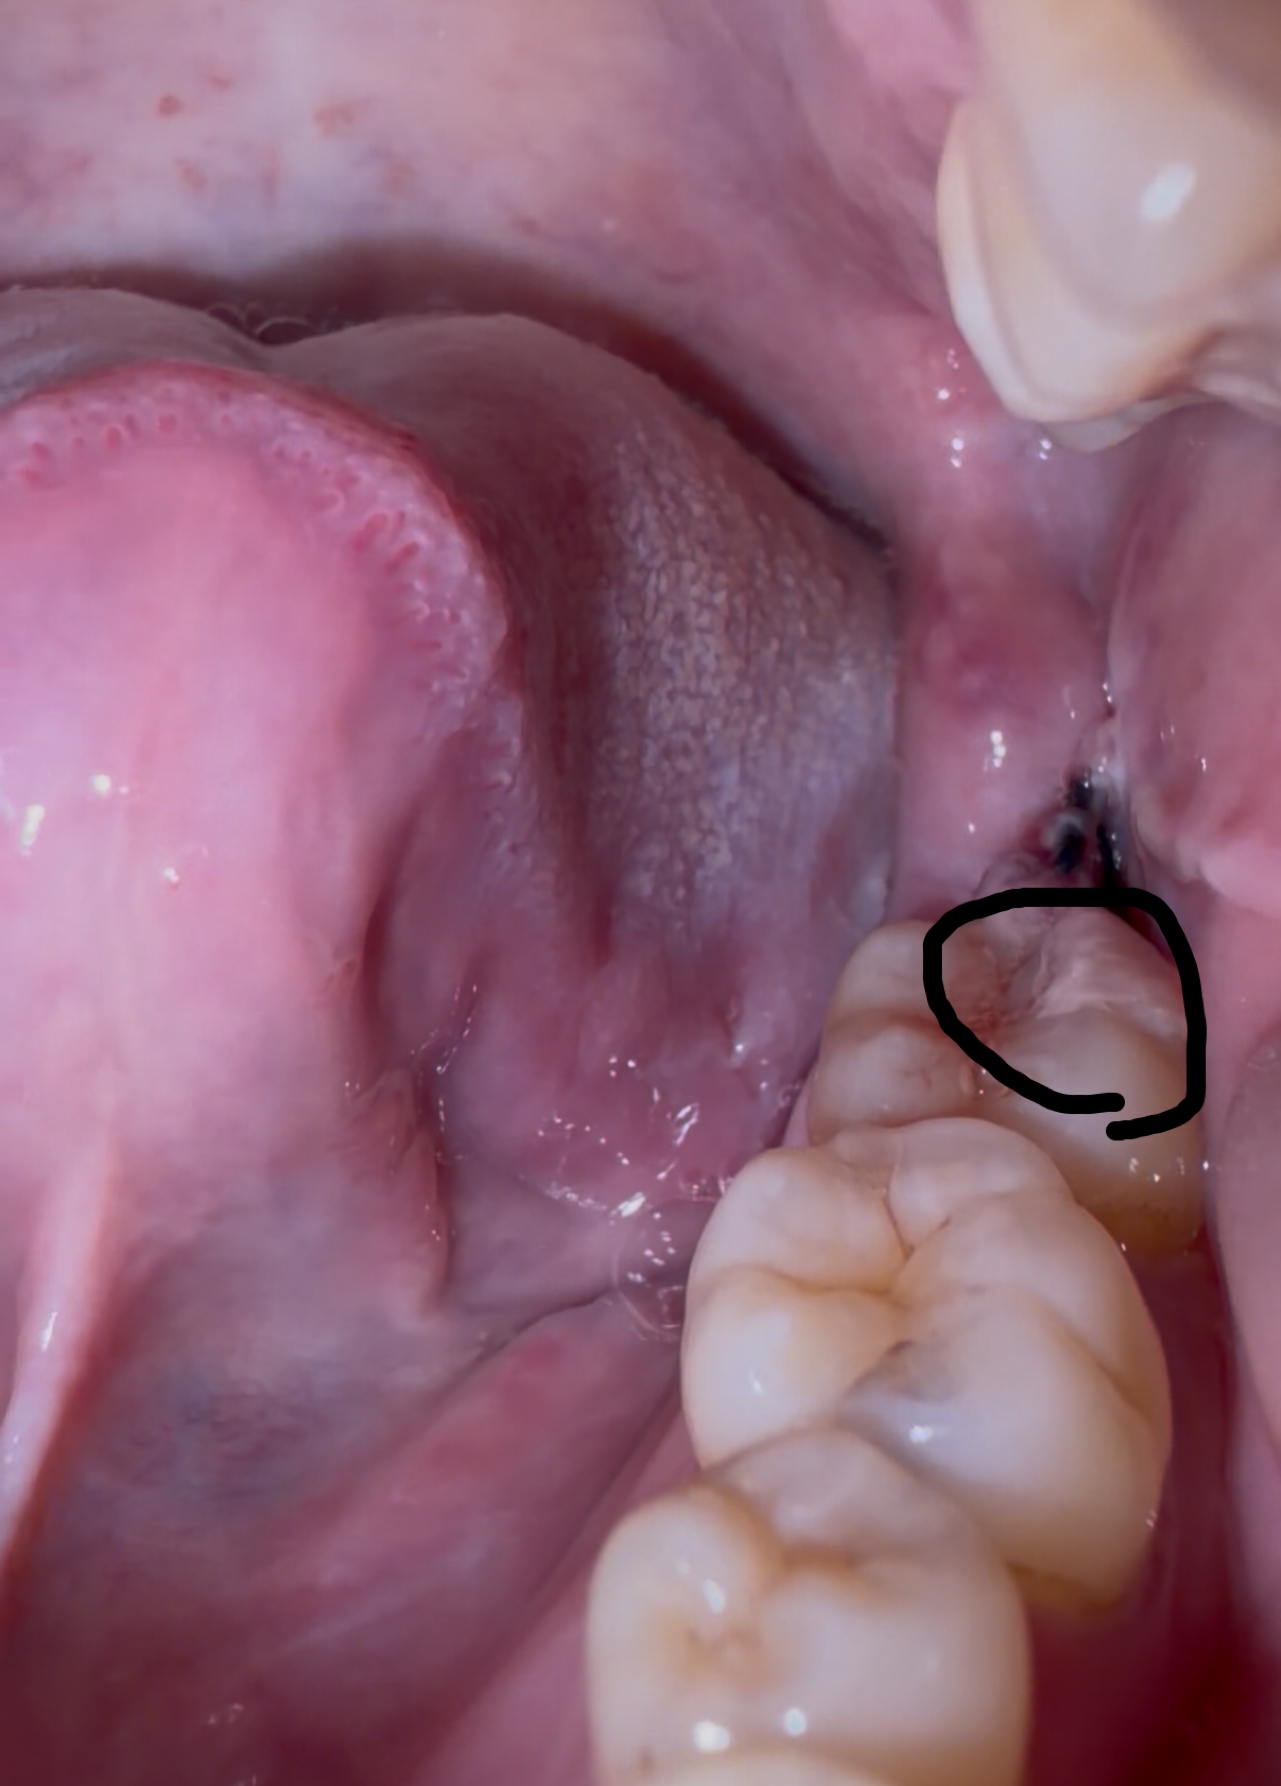

親知らず抜歯後、大きな血餅が出来ました。取れたらドライソケットになりますか?